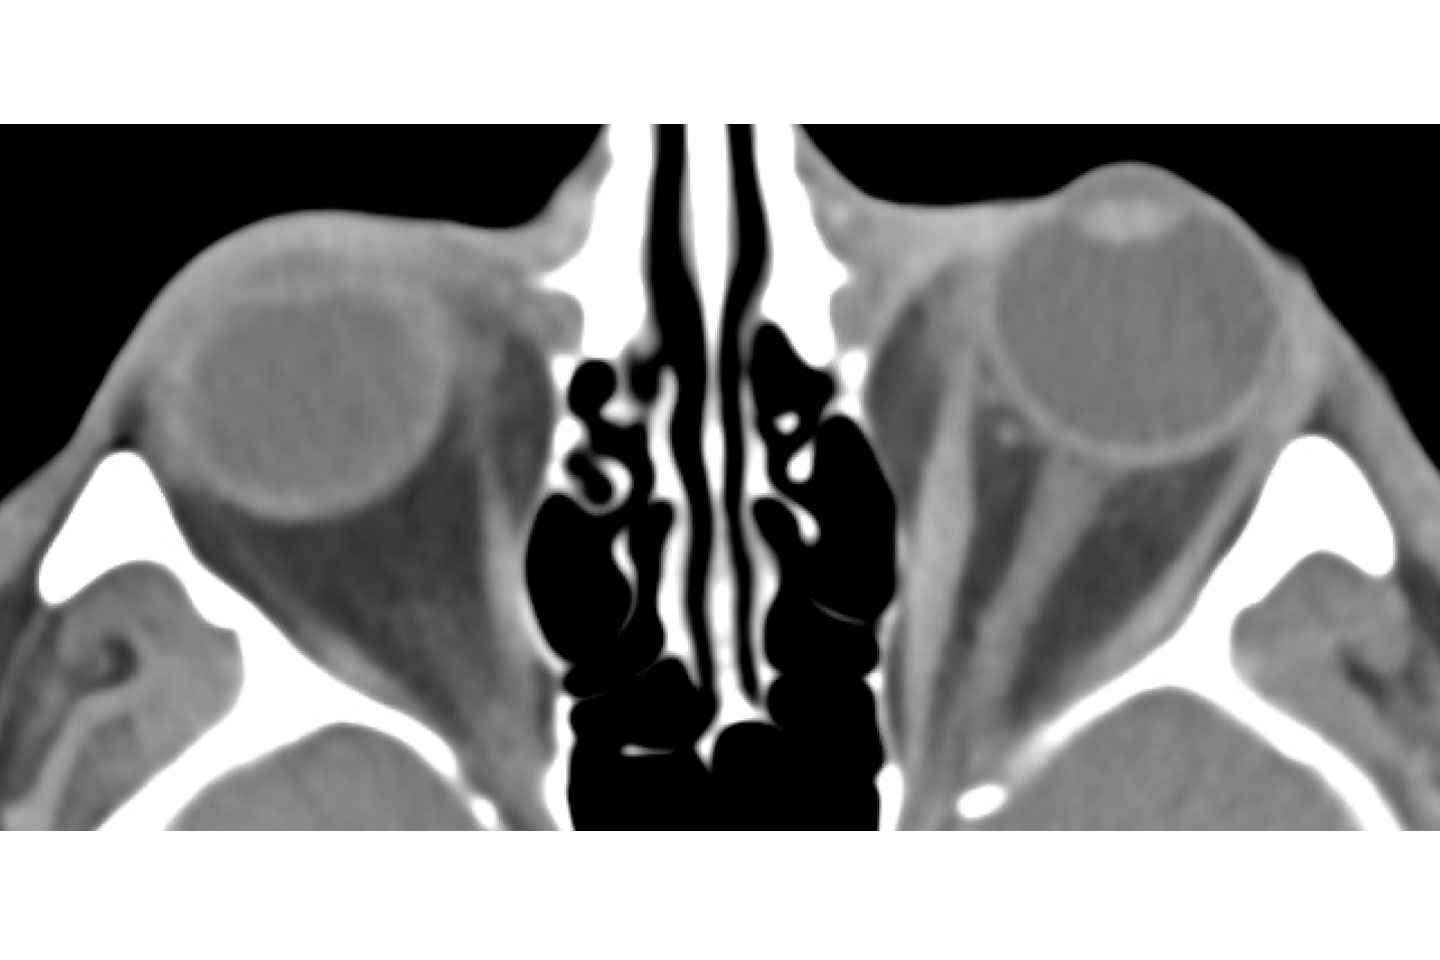

Coronal postoperative imaging showing relief of orbital pressure. Source: NYU Langone Health